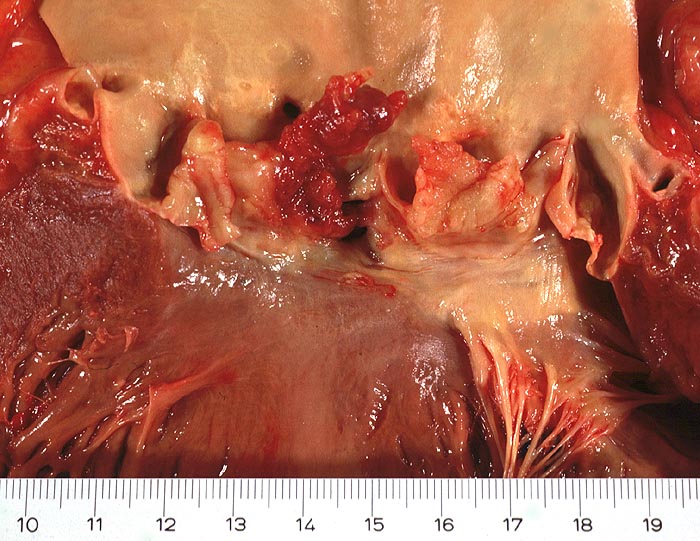

AP/ Infektiöse Endocarditis ulcero-polyposa

Infektiöse Endocarditis ulcero-polyposa

Makroskopisch sind entweder flache rötliche fibrinbelegte Ulzera (=ulcerosa (> 2935)) oder zusätzlich weiche gelbbraune bröcklige erbs- bis pflaumengrosse Polypen (=ulceropolyposa (> 2936) (> 8376)) oder ausschliesslich polypoide Fibrinbeläge (=marantica) auf einem Endokarddefekt oder einer partiell zerstörten Klappe erkennbar.

Histologisch findet sich bei ulzeropolypöser Endokarditis ein Fibrin-Thrombozytenthrombus, welcher von Bakterien durchsetzt ist (=Vegetation). Die Vegetation sitzt auf einem Klappendefekt an dessen Basis Granulationsgewebe einzusprossen beginnt, welches den Thrombus organisiert. Klappendefekte, Gefässeinsprossungen, verdickte Sehnenfäden (> 2848) oder Kommissurenverwachsungen (> 8389) der Taschenklappen weisen morphologisch auf eine abgeheilte Endokarditis hin.

• Längsschnitt durch Aorta, Aortenklappe und linkes Ventrikelmyokard.

• Oben im Bild die Aorta mit kleinem Fibroatherom.

• Abszedierende Entzündung der aortalen Adventitia ausgehend von septikopyämischen Streuherden.

• Ulzerierte Aortenklappe(ulcerosa).

• Dem ulzerierten Klappengerüst aufgelagerte polypöse Vegetation aus Fibrin und Granulozyten durchsetzt von blauen Kokkenbakterienkolonien (polyposa).

• Ausgedehnte frische Koagulationsnekrose (unsichtbare Zellkerne, Infiltrate neutrophiler Granulozyten) des linken Ventrikelmyokards unterhalb der Klappe.

• Mehrere septikopyämische Streuherde (blaue Bakterienhaufen in intramyokardialen Blutgefässen umgeben von Mikroabszessen).